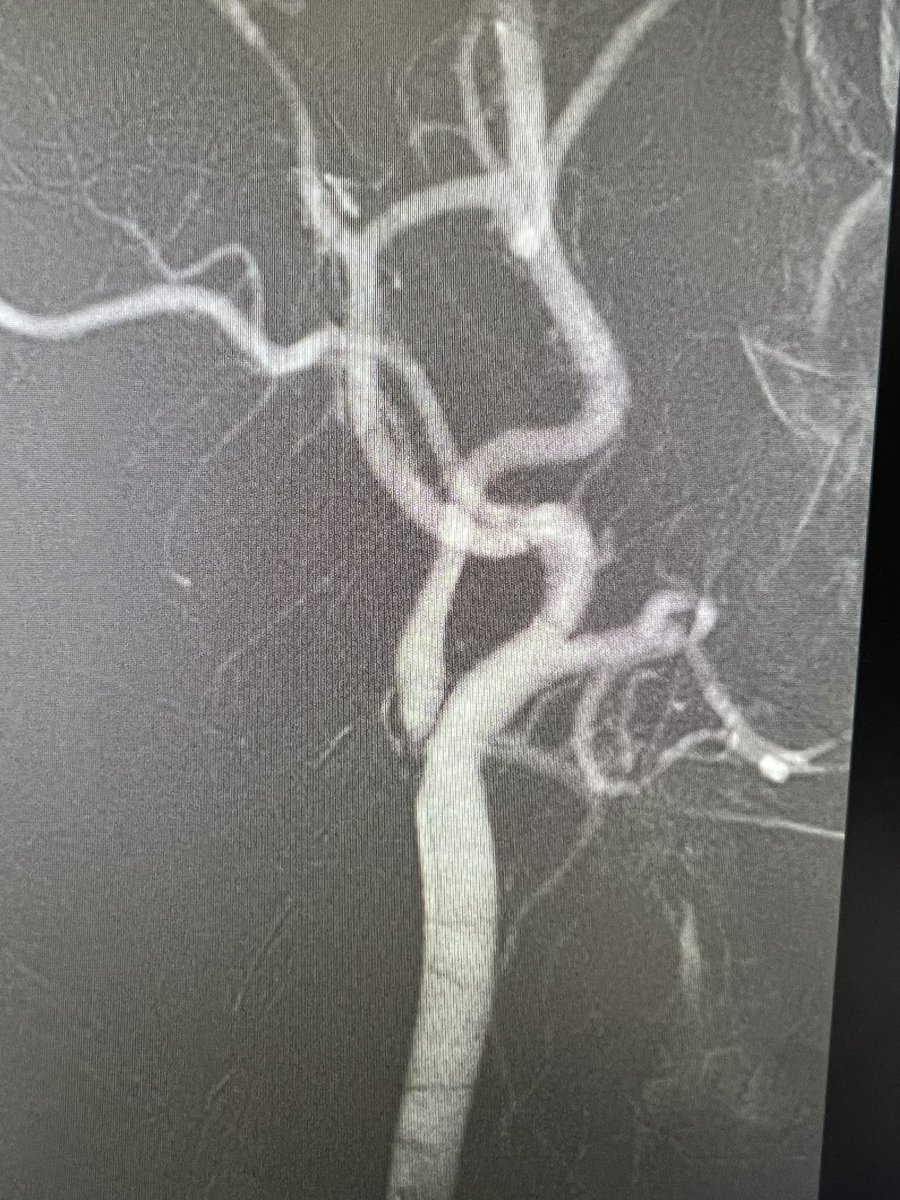

48y, ílio-popliteal dvt, symptomatic. angiographic control after ClotTriever. No thrombolytic, no cti needed. @InariMedical